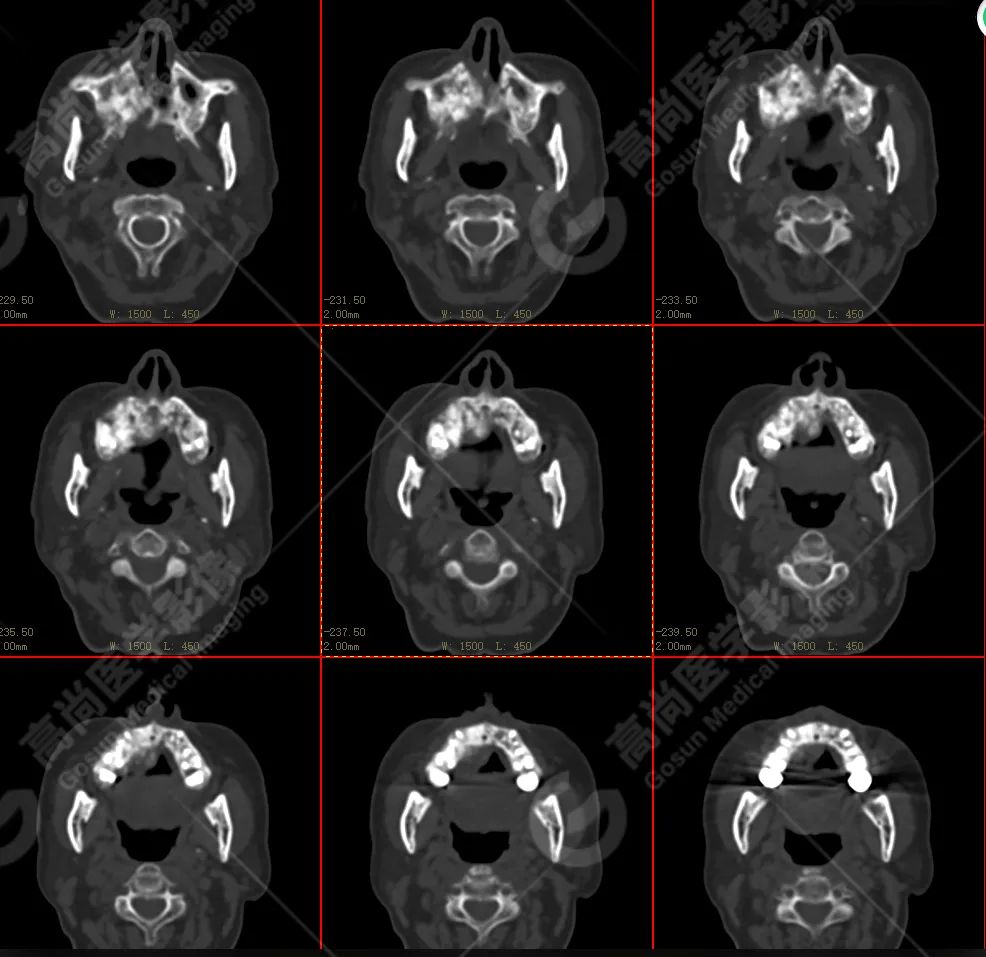

右侧上颌骨-上颌窦骨壁-骨性鼻中隔区域见片块状放射性摄取异常增高影,最大层面约 4.1 cm×3.8 cm×2.8 cm,SUV 最大值为 10.4,CT 示上述部位见成骨性改变,骨质不均匀弥漫性增厚、密度不均匀增高,并可见肿瘤骨影,边缘毛糙,周围伴软组织增厚。